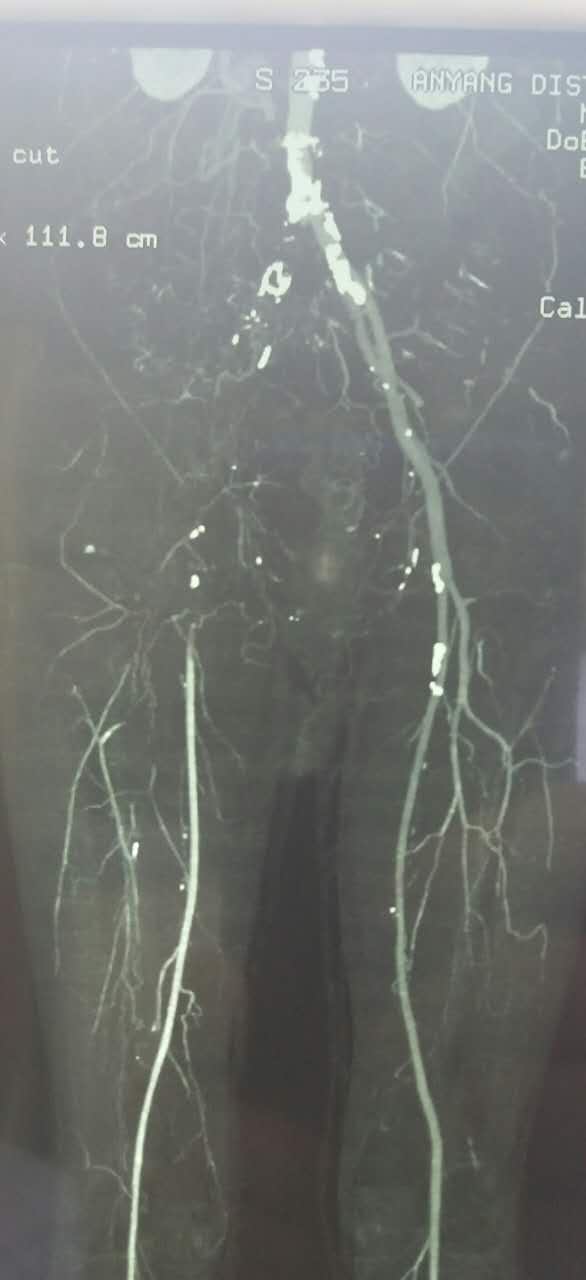

54岁男性,右足疼痛半月余。患者半月前无明显诱因突发右下肢疼痛,行走后加重,休息减轻。超声提示腹主动脉左髂动脉多发狭窄闭塞,右髂动静脉闭塞。CTA

对比正常解剖模式图,我们可以发现:右侧髂总髂内髂外股总动脉未显影,股深动脉未显影,右侧股浅动脉起始段未见显影,考虑有血栓闭塞的可能。